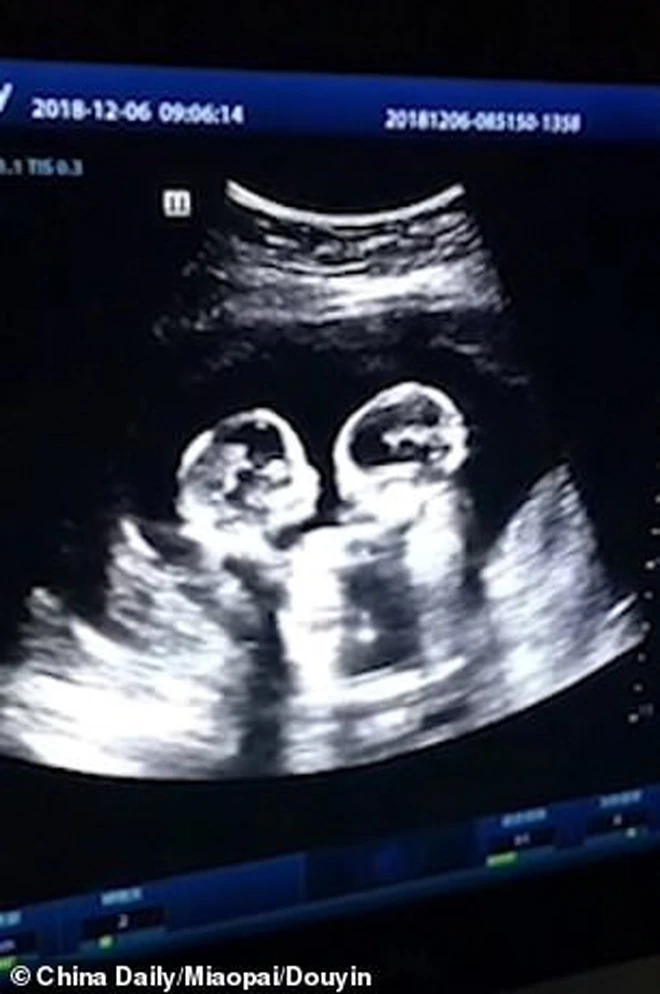

In a moment that lit up both the country and pop music worlds, Kelly Clarkson and Brett Eldredge shared some life-changing news during a surprise joint appearance this past weekend in Nashville: Kelly Clarkson is four weeks pregnant—with twins. The announcement came during an emotional, unscripted exchange between the two stars that left the live audience stunned and the internet buzzing with excitement, curiosity, and celebration.

“I wasn’t sure if tonight was the right time,” she said with a smile, one hand resting lightly on her stomach. “But standing here with someone who’s been such a beautiful part of my musical journey, and in front of fans who’ve walked with me through so much… I just feel like I need to say it. I’m four weeks pregnant—with twins.”